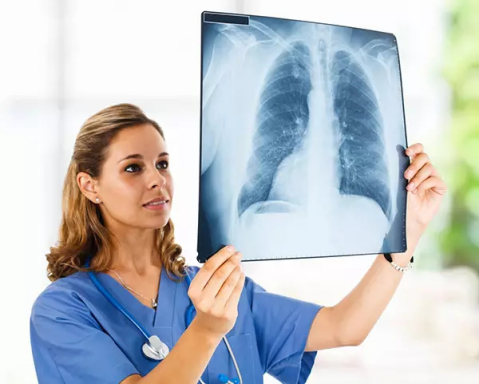

3、胸部——粗看X光平片,細(xì)看CT

X光胸片可粗略檢查肺、心影、主動(dòng)脈弓、肋骨等,可以檢查有無肺紋理增多、肺內(nèi)較大腫塊、主動(dòng)脈結(jié)鈣化等。胸部CT檢查顯示出的結(jié)構(gòu)更清晰,對(duì)胸部病變檢出敏感性和準(zhǔn)確性均優(yōu)于常規(guī)X光胸片,特別是對(duì)于篩查早期肺癌有重大意義。而磁共振成像對(duì)于肺內(nèi)疾病的診斷,應(yīng)用非常有限。